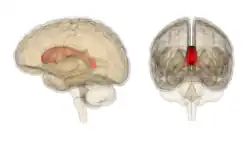

![]() Corpus callosum from above, front part at the top of the image | |

The corpus callosum (Latin for "tough body"), also callosal commissure, is a wide, thick nerve tract, consisting of a flat bundle of commissural fibers, beneath the cerebral cortex in the brain. The corpus callosum is only found in placental mammals.[1] It spans part of the longitudinal fissure, connecting the left and right cerebral hemispheres, enabling communication between them. It is the largest white matter structure in the human brain, about 10 cm (3.9 in) in length and consisting of 200–300 million axonal projections.[2][3]

The corpus callosum forms the floor of the longitudinal fissure that separates the two cerebral hemispheres. Part of the corpus callosum forms the roof of the lateral ventricles.[5]

The corpus callosum has four main parts – individual nerve tracts that connect different parts of the hemispheres. These are the rostrum, the genu, the trunk or body, and the splenium.[4] Fibres from the trunk and the splenium, known together as the tapetum ("carpet"), form the roof of each lateral ventricle.[6]